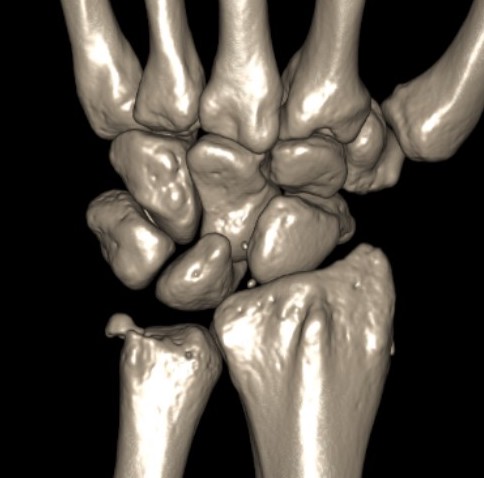

Isolated dorsal dislocation DRUJ

Isolated dorsal DRUJ instability with ulna sided TFCC tear

MRI demonstrating dorsal distal ulna subluxation associated with significant ligament disruption